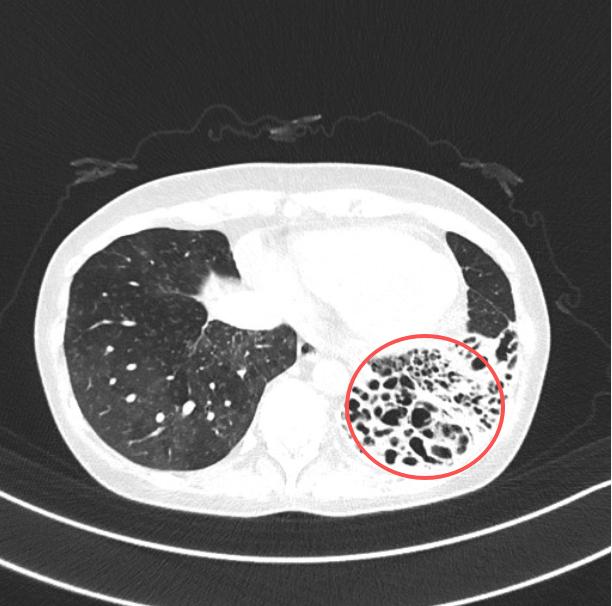

被推进北大深圳医院急诊大厅时,急诊科立即启动急危重症孕产妇绿色通道,值班急诊医生快速评估患者的血压已接近休克阈值,心率100/分,血氧饱和度95%CT显示左下肺、左上肺舌段、右中肺支气管扩张。